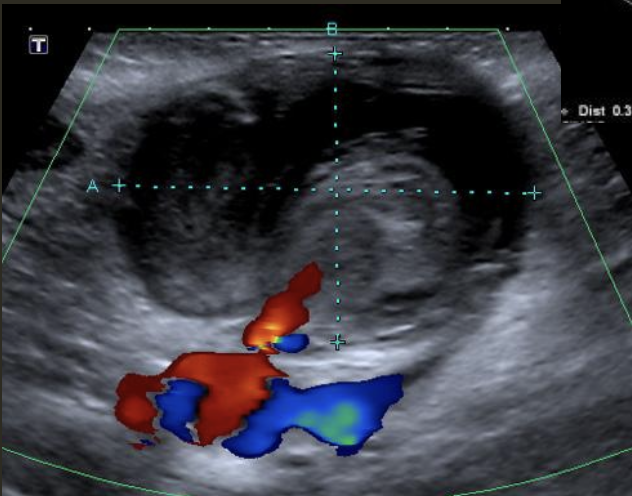

Pseudoaneurysm → rupture from intima layer contained in deeper layers of artery wall

2D US presentation: heterogenous, pulsating central structure with internal swirling of brighter echogenicity

color doppler: “yin-yang” sign, “to and fro” PW waveform

DDX: hematoma (hypoechoic intraluminal echoes, but not color flow or neck connecting), true aneurysm (wide rather than narrow neck continuous w/ artery, chronic rather than acute)